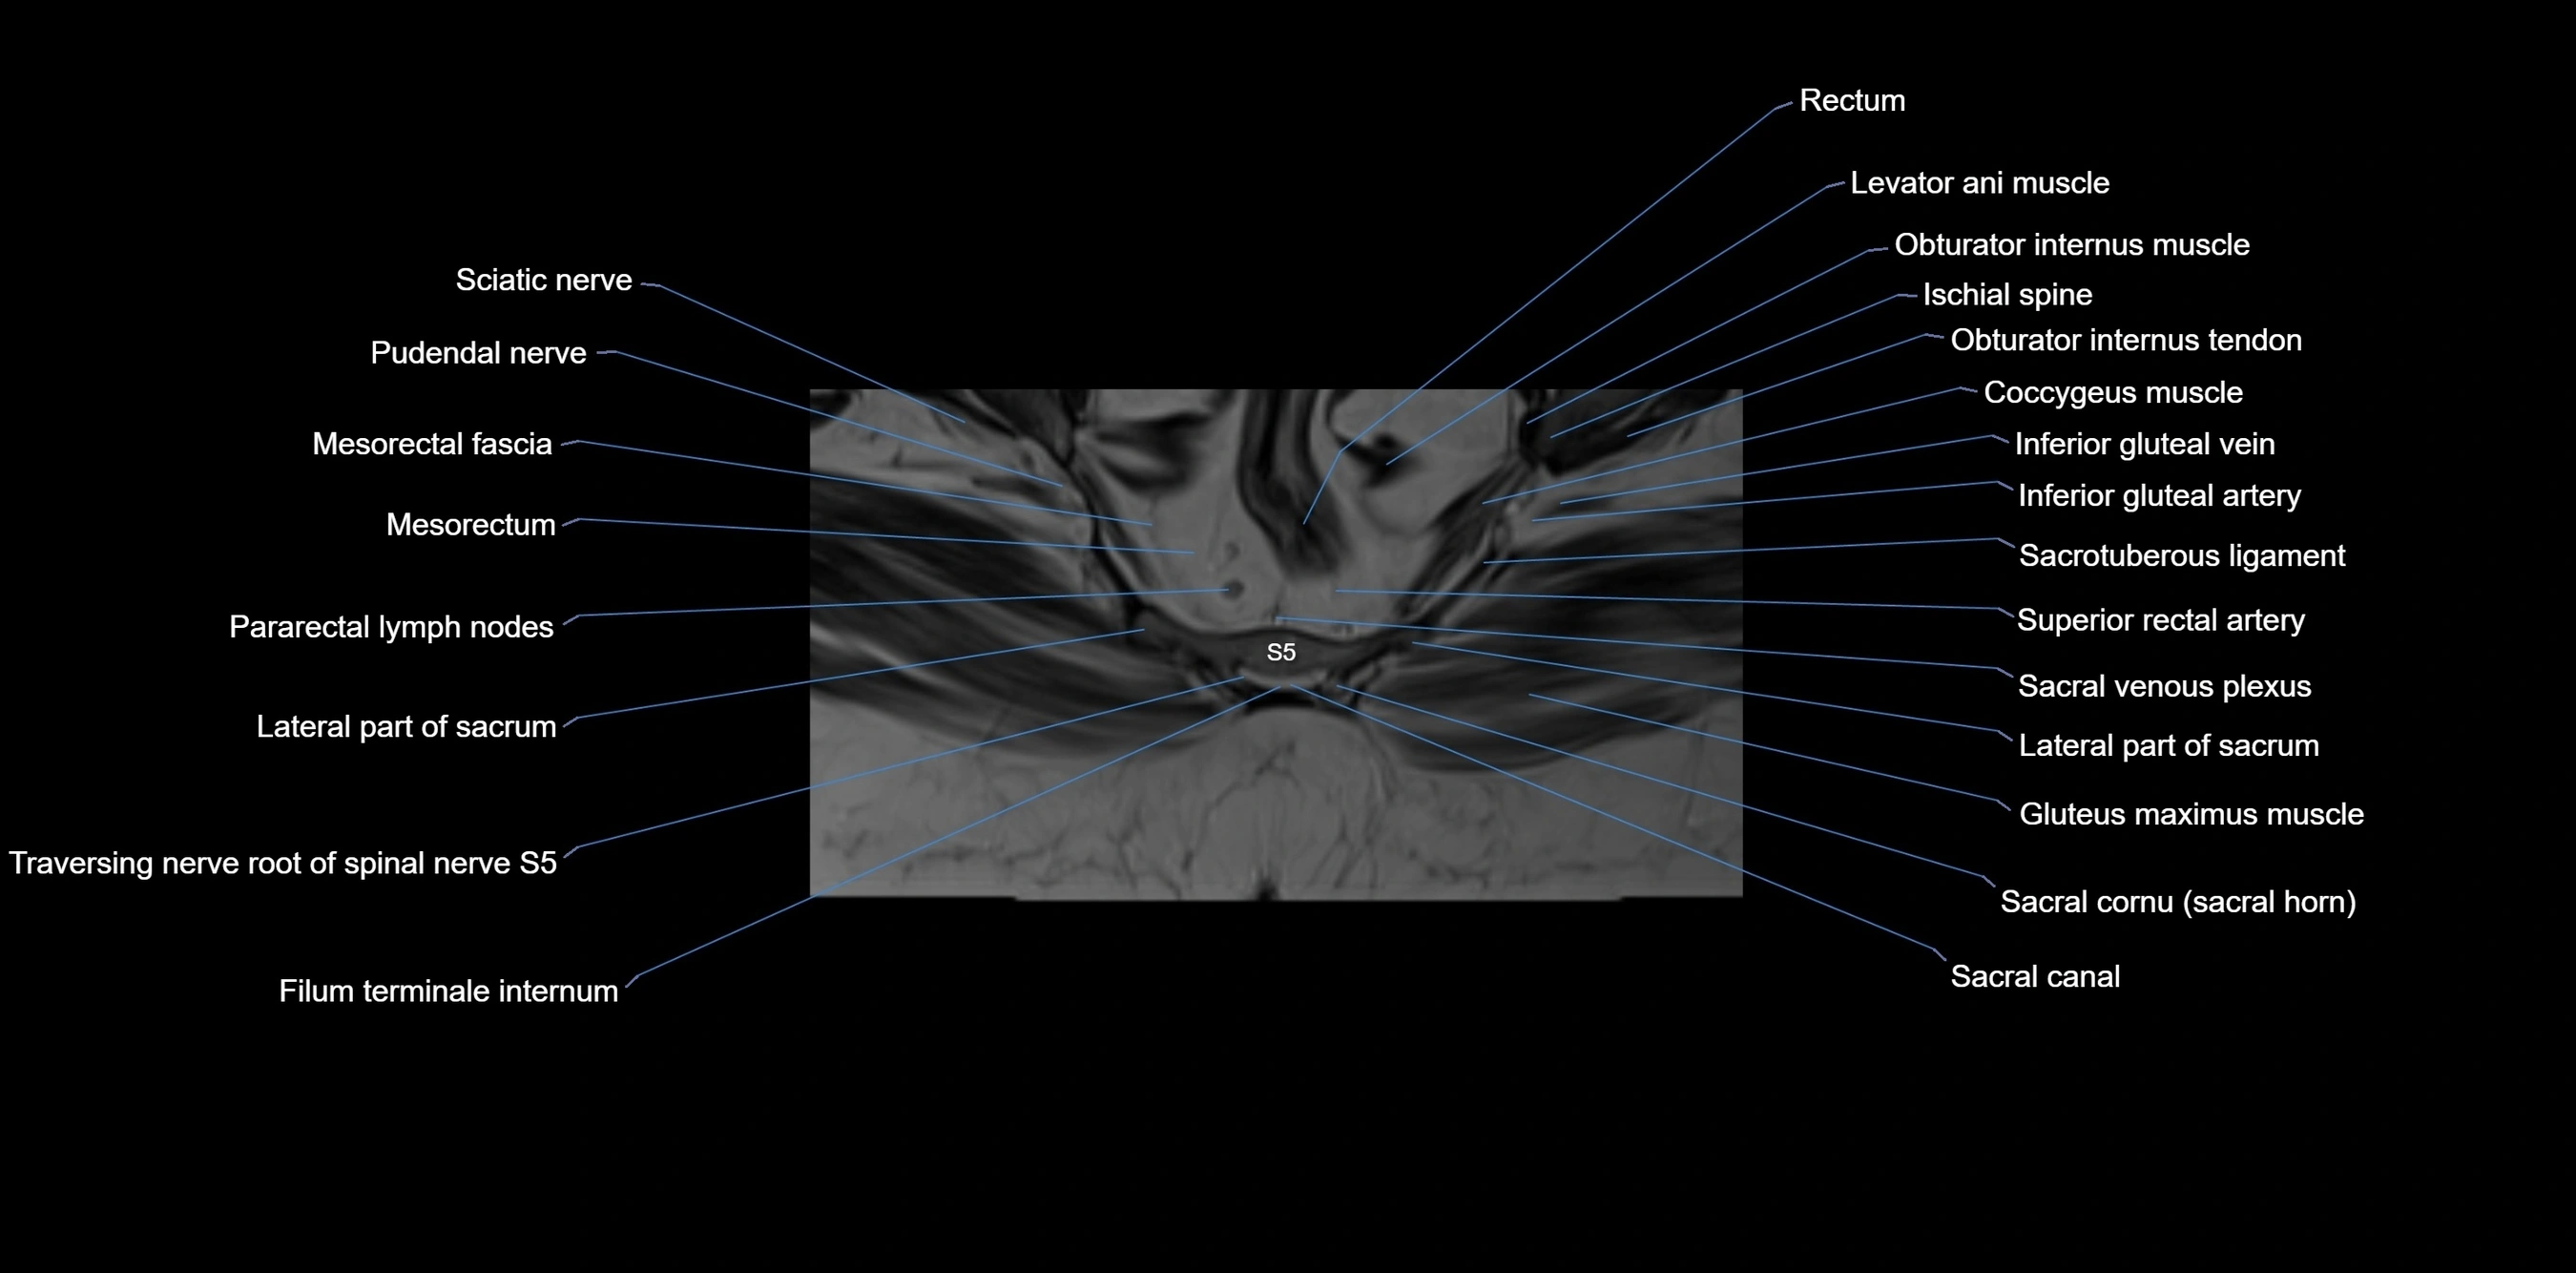

MRI Appearance

T1-weighted images:

• Cortical bone appears very low signal (dark); marrow shows intermediate signal

• Iliac fossa fat is bright against low-signal cortex

T2-weighted images:

• Cortical bone remains dark

• Marrow signal varies depending on fat content; edema or tumor shows hyperintensity

STIR:

• Suppresses fat, making bone marrow edema, fractures, or infiltrative lesions appear bright

• Excellent for trauma, sacroiliitis, and metastatic evaluation

T1 Fat-Saturated (Pre-contrast):

• Marrow: intermediate signal, fat suppressed

• Useful for detecting subtle marrow abnormalities adjacent to iliac cortex

T1 Fat-Saturated Post-Contrast (Gadolinium):

• Enhances vascularized structures, marrow pathology, tumors, and inflammatory changes

• Highlights soft tissue or bone invasion in pelvic neoplasms

MRI Non-Contrast 3D Imaging:

• Provides 3D morphology of iliac wing, crest, and articulations

• Used in preoperative planning for pelvic surgery and trauma reconstruction

MRI image

image